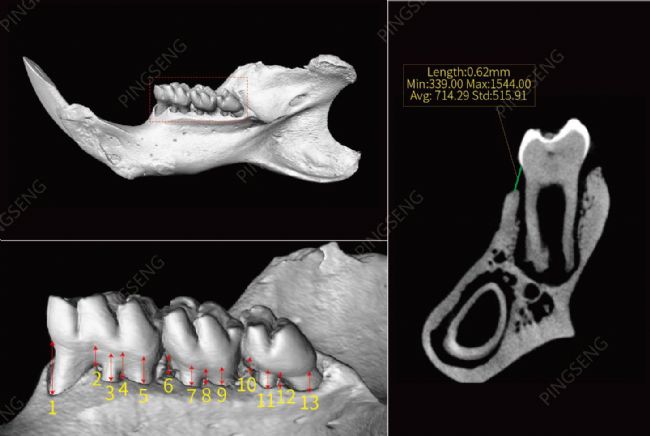

實例2:大鼠下頜骨和舀齒

大鼠或小鼠下頜骨和臼齒在牙周病和其他牙科相關(guān)領(lǐng)域的許多研究模型中有著重要價值。通過顯微CT對動物下頜骨和牙齒的測量研究,可進一步分析牙周生物型各特征之間的相關(guān)性,為口腔美學(xué)修復(fù)、種植治療方案的選擇、治療預(yù)后的判斷以及療效的評估提供理論基礎(chǔ)

圖5:大鼠下頜骨和舀齒的3D渲染

圖6:選取每個牙齒的牙槽突到齦緣的最大和最小距離點,并在單個切片上測量。

圖7: a1、b1、c1、d1分別是a區(qū)、b區(qū)、c區(qū)、d區(qū)的頂部切面,a2、b2、c2、d2分別是幾個區(qū)的底部切面;最右側(cè)圖顯示了在a、b、c 區(qū)任選一切面上,分別展示了在Avatar軟件上手繪不規(guī)則ROI、標(biāo)準(zhǔn)橢圓ROI及標(biāo)準(zhǔn)方型ROI后,可自動計算感興趣區(qū)域的尺寸及區(qū)域內(nèi)骨小梁的密度均值、標(biāo)準(zhǔn)差和最大、最小值。同時,可對感興趣區(qū)域的骨小梁的其他參數(shù)進行定量分析。